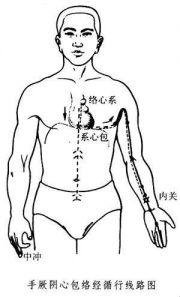

| 2021年7月26日 (一) 20:03 | 心包经循行线路图.jpg (文件) |  |

38 KB | Uploaded with SimpleBatchUpload | 3 |